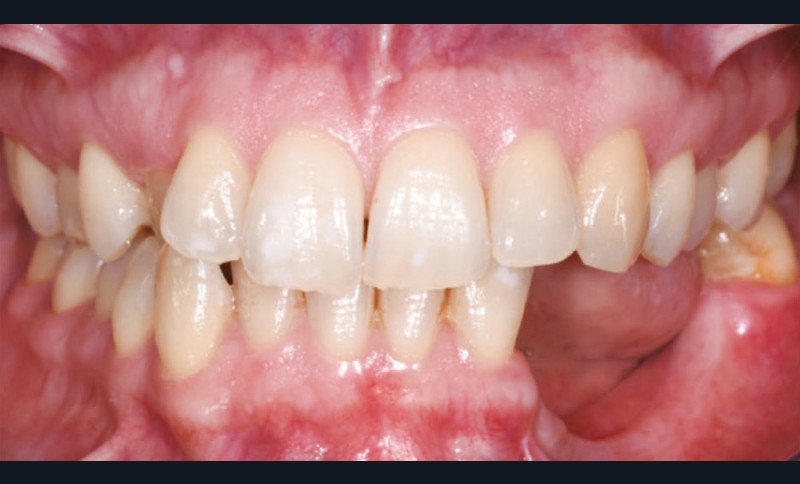

L’examen facial est sans particularités notables. L’examen buccal retrouve un édentement de 33 à 36, compensé par une prothèse amovible, avec une atrophie osseuse transversale et verticale majeure entraînant une augmentation de l’espace prothétique. Il persiste un fin bandeau de gencive kératinisée crestal. Le reste de la denture est sain, l’articulé est en classe I avec un inversé d’articulé sur 13 (fig. 1).